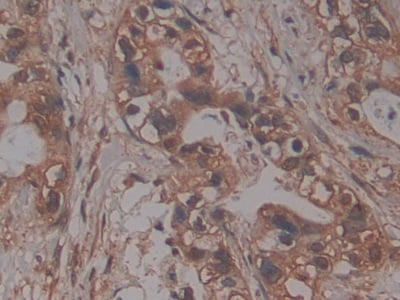

IHC (Immunohistochemistry)

(Immunoperoxidase of monoclonal antibody to PDK2 on formalin-fixed paraffin-embedded human salivary gland. [antibody concentration 0.8ug/ml])